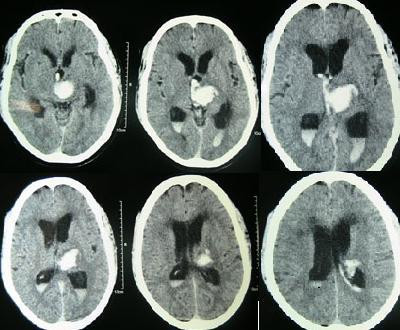

С учетом вышеизложенного был разработан альтернативный метод лечения гидроцефалии - вентрикулосинустрансверзостомия. Суть его заключается в следующем: проводится стандартная установка вентрикулярного катетера в полость бокового желудочка мозга, затем соединение его с клапаном фиксированного или программированного давления. После происходит погружение катетера в поперечный синус головного мозга. Хирургом производятся только два небольших разреза на голове, что является преимуществом данной методики.

Это физиологический метод лечения, так как цереброспинальная жидкость в организме здорового человека всасывается из пахионовых грануляций арахноидальной оболочки головного мозга и поступает через венозные синусы в венозную систему. Таким образом, с помощью вентрикулосинустрансверзостомии обеспечивается физиологический отток ликвора в венозную систему головного мозга.

1.Расширенный боковой желудочек головного мозга;

2.Катетер установленный в полость бокового желудочка;

3.Клапанное устройство шунтирующей системы;

4.Катетер установленный в поперечный синус;

5. Поперечный синус